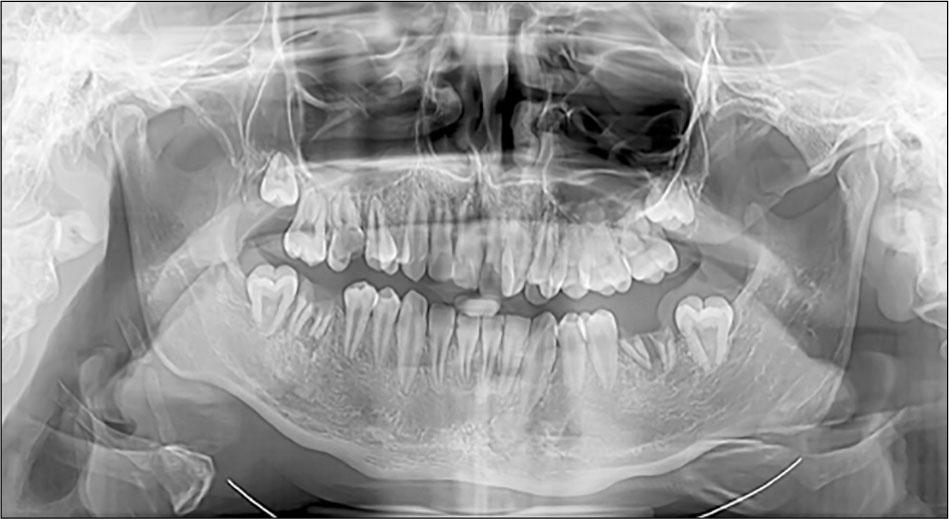

Through correlation with the orthopantomography, the following aspects were highlighted (Figures 5, 6): the right superior central incisor insufficiently erupted, rotated mesially; both incisors with slight palatoversion; transposition between the left lateral incisor and canine. In addition, the patient has an open bite and the median line is deviated to the right. Supplementary, we found agenesis of third inferior molars on the orthopantomography (Figure 6).

Orthopantomography at 16 years